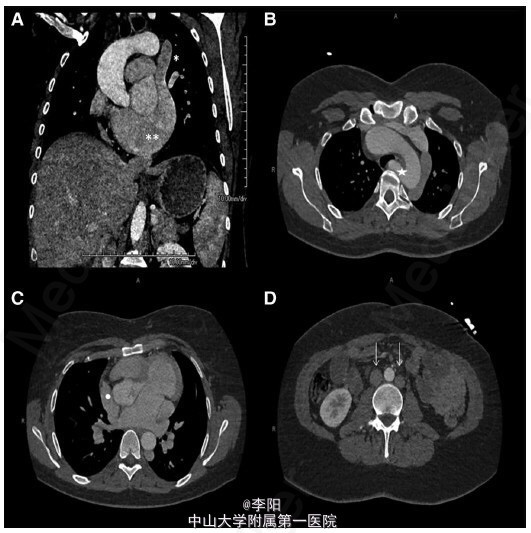

患者,女,35 岁,因车祸入院,既往曾行直肠阴道瘘修补术,诉劳力性呼吸困难多年。面部特征表现为双侧耳前凹陷、脸部不对称。查体提示左侧第二肋间舒张期杂音。血常规、心电图、胸片均未见异常。超声心动图提示升主动脉扩张(39mm),主动脉瓣重度反流。经食管超声心动图提示四叶式主动脉瓣(图 1A-1C)。增强 CT 显示双下腔静脉系统、半奇静脉及持续性上腔静脉异常,冠状动脉窦动脉瘤并主动脉四叶瓣 (图 2A-2D)。